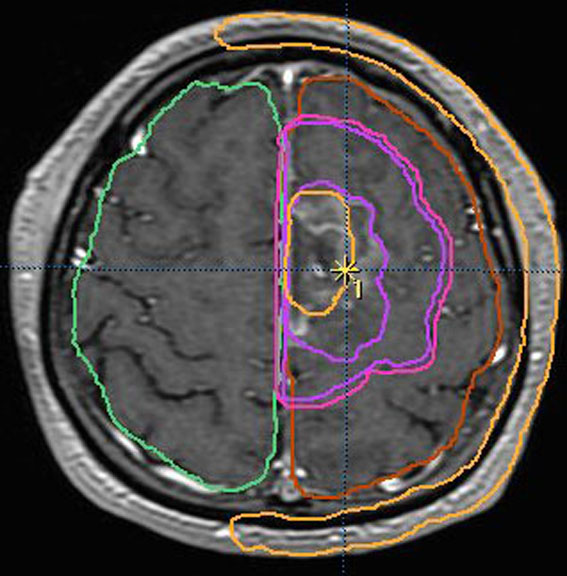

放射線治療計画の等線量曲線 isodose curves です

腫瘍とその周辺にどの程度の線量(グレイ)を当てるかを計画します

赤紫の線で囲われた部分が,実際に計画線量をかける部分(照射野,PTV)です

グリオーマでは,MRIでみえている腫瘍範囲よりかなり広い領域の正常脳にも放射線がかかります

MRIでみえる腫瘍の領域を腫瘍体積 (GTV)といいます

オレンジの色がGTVではっきり腫瘍と断定できるところです

グリオーマはMRIでみえる以上に広がっているので,腫瘍の周囲を十分に囲む領域を照射します,それを臨床的標的体積 (CTV)といいます

赤紫の線で囲った部分の内側で,びまん性グリオーマの場合は,GTVから20mmくらいの距離を取るのが普通です

さらに少し (0.3-0.5cm) 領域を広げてかけ損じのないようにするので治療計画表的体積 (PTV)といいます,上の図では赤紫の2本の線の外側にあたります

薄茶色に塗った部分には計画54グレイの90%以上の線量が入ります

この体積の決め方は腫瘍の形や悪性度によっても変わってきます

放射線治療医の腕の見せ所です

実際に放射線があたるのはPTVの領域です

この例の治療計画でとても大切な点は,腫瘍のある左前頭葉には放射線が十分入っているのですが,右前頭葉の被曝は最低限に抑えられている点です

両側の前頭葉の対照的な被曝では認知機能が著しく低下することを知っている放射線治療医だからできることです